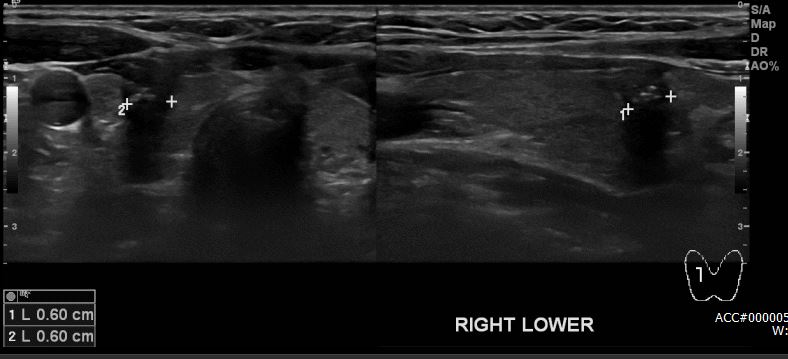

상기환자 최근 급격히 피곤하고 , 붓고, 탈모 증상 있어 내원하신 40대 여성 분으로

본원 갑상선 초음파상 우측갑상선 하부에 의심 스런 멍울 있어 세침검사 시행하여

우측 갑상선 유두암 진단 되었습니다.